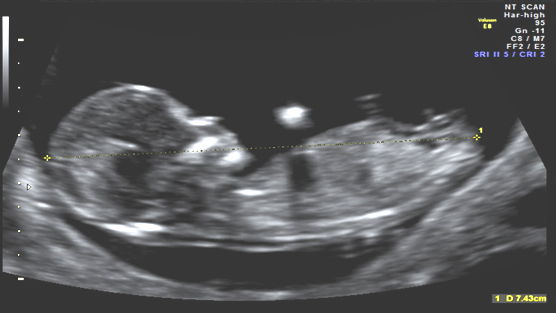

What is combined first trimester screening?

Combined first trimester screening involves the markers of the ultrasound (popularly called as NT, NB scan) and the blood test- dual marker test. These markers on the scan and the values of the blood test together when combined, provides a risk assessment which tells us that the pregnancy is at high risk or not for genetic abnormalities like Trisomy 21 (Downs syndrome). For risk assessment, we use a software provided by Fetal Medicine Foundation, UK.

The aim is to establish that the baby is alive or not and correctly, establish its gestational age. It involves assessing the baby for gross structural abnormalities. The most important aspect is to assess certain markers like fluid behind the neck of the baby (nuchal translucency), presence of nasal bone, blood flows through heart (tricuspid Doppler) and tummy (ductus venosus) and heart rate.